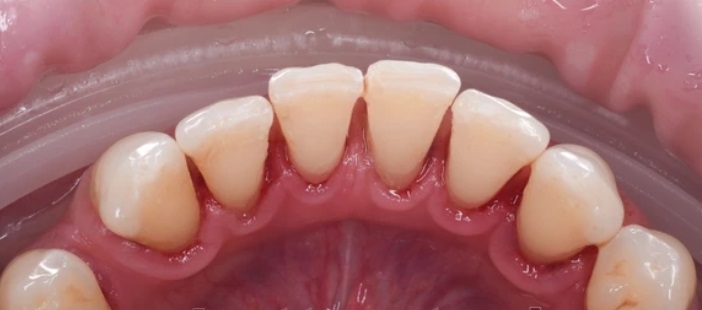

Проблема

У пациента выраженные зубные отложения и пигментированный налёт, особенно в области нижних и верхних передних зубов, с воспалённым краем десны.

Решение

Проведена профессиональная гигиена полости рта — налёт и камень удалены, зубы стали заметно чище и светлее, состояние десны улучшилось.